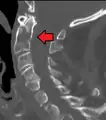

Position of axis (shown in red)

In anatomy, the axis (from Latin axis, "axle") is the second cervical vertebra (C2) of the spine, immediately inferior to the atlas, upon which the head rests.

The axis' defining feature is its strong odontoid process (bony protrusion) known as the dens, which rises dorsally from the rest of the bone.

The dens, also called the odontoid process, or the peg, is the most pronounced projecting feature of the axis. The dens exhibits a slight constriction where it joins the main body of the vertebra. The condition where the dens is separated from the body of the axis is called os odontoideum and may cause nerve and circulation compression syndrome.[1] On its anterior surface is an oval or nearly circular facet for articulation with that on the anterior arch of the atlas. On the back of the neck, and frequently extending on to its lateral surfaces, is a shallow groove for the transverse atlantal ligament which retains the process in position. The apex is pointed and gives attachment to the apical odontoid ligament. Below the apex, the process is somewhat enlarged and presents on either side a rough impression for the attachment of the alar ligament; these ligaments connect the process to the occipital bone.